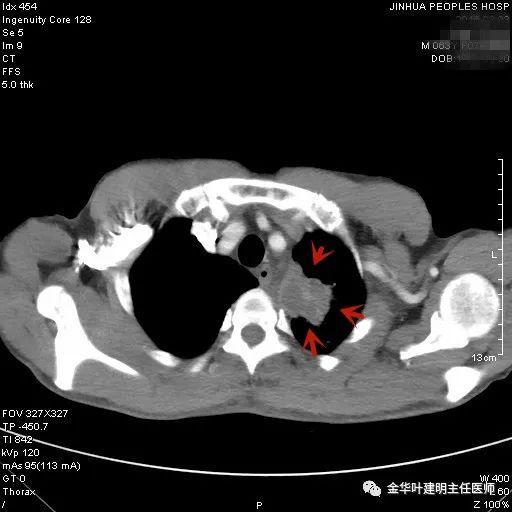

叶建明谈结节:检查发现肺实性结节怎么办?个人版实用指南

上图是结核,但这么明显的左上肺占位,谁又能从影像上排除它是肺癌呢?当然回头看,病灶中间密度低(可能液性)、周围一圈强化明显些、与纵隔组织关系密切但没有明显侵犯,界限仍然清楚,是有良性可能的。